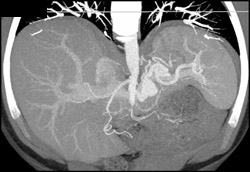

Collaterals in 3D